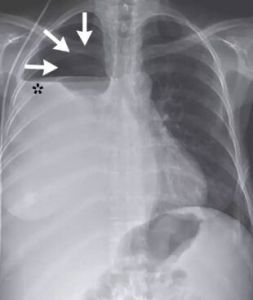

1、阻塞性(吸收性)肺萎陷:由於支氣管被附近腫大的淋巴結或瘤塊壓迫,或支氣管被腫瘤、異物、血凝塊等阻塞,致空氣不能進入所屬末梢肺組織,其中原有的空氣漸被吸收而導致一群小葉甚或整個肺葉無氣和皺縮。

2、壓縮性肺萎陷:大量胸腔積液,自發性氣胸,嚴重的脊柱變形或腹腔巨大腫瘤或大量腹水使膈抬高,從而壓迫肺組織,使肺泡陷閉而無氣。